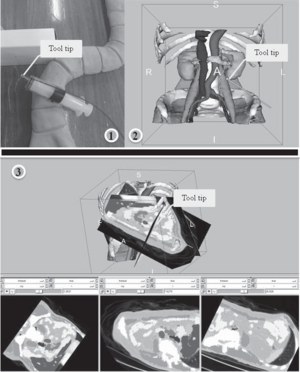

- 5.23 Augmented Reality Visualization using Image Overlay Technology for MR-Guided Interventions: Cadaveric Bone Biopsy at 1.5 T

- 5.36 Augmented Reality Visualisation Using an Image Overlay System for MR-guided Interventions: Technical Performance of Spine Injection Procedures in Human Cadavers at 1.5 Tesla